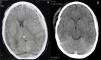

ConclusionsThere are two main mechanisms for the spontaneous resolution of acute subdural haematomas: dilution in subarachnoid space and redistribution of the haematoma in the subdural space. The primary radiological characteristic of these lesions is a hypodense rim on the outer surface of the clot. Spontaneous resolution of TASDH is unusual. Clinical and radiological surveillance is essential for appropriate management of these patients.

ConclusionesExisten 2 mecanismos principales para la resolución espontánea de hematomas subdurales agudos: la dilución en el espacio subaracnoideo y la redistribución del hematoma en el espacio subdural. La principal característica radiológica de estas lesiones es una cerco hipodenso en la superficie exterior del coágulo. La resolución espontánea de HSDAT es rara. La vigilancia clínica y radiológica es esencial para el manejo adecuado de estos pacientes.